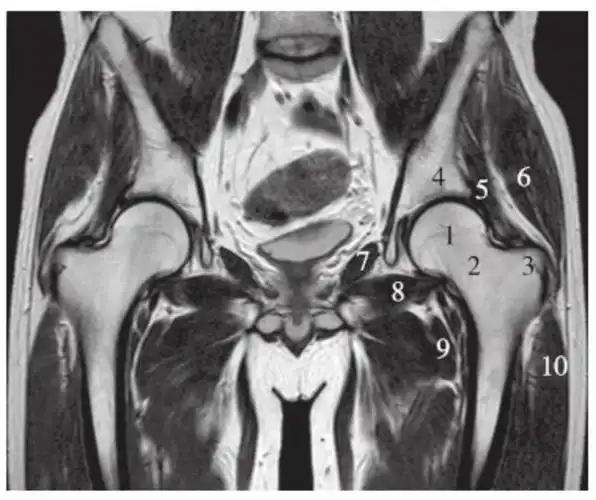

一文掌握正常髋关节mri解剖示意图